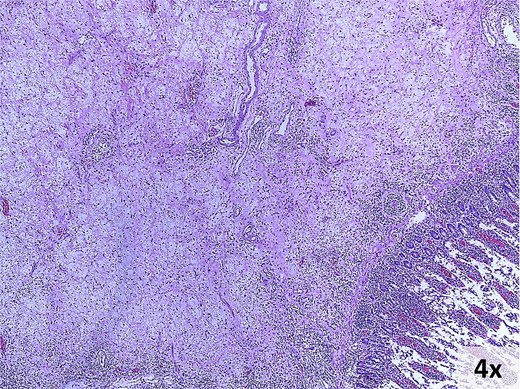

Pathology revealed a 9 × 8 × 3 cm ileocecal tumor with negative margins and uninvolved lymph nodes (Fig. 4). Microscopically, the tumor comprised fibroconnective stroma with hypercellularity of myofibroblastic spindle cells arranged in a storiform pattern, along with prominent lymphoplasmacytic infiltrate (Fig. 5). Immunohistochemistry showed positivity for muscle-specific actin (MSA), vimentin, and focal desmin; Ki-67 index was 5%; calretinin, beta-catenin, and anaplastic lymphoma kinase (ALK) were negative (Fig. 6). These findings confirmed an IMT diagnosis.

Microscopic findings. Hematoxylin and eosin-stained photomicrograph of the lesion.

Grossly, IMTs present as well-circumscribed, multinodular masses with pushing margins and a white-gray, yellow, or tan coloration, measuring 1–20 cm (mean: 4–8 cm). Microscopically, the tumor cells exhibit vesicular nuclei, small nucleoli, and pale eosinophilic cytoplasm. Three basic histological patterns may coexist within the same tumor: myxoid, hypercellular, and hypocellular [1, 8, 9].